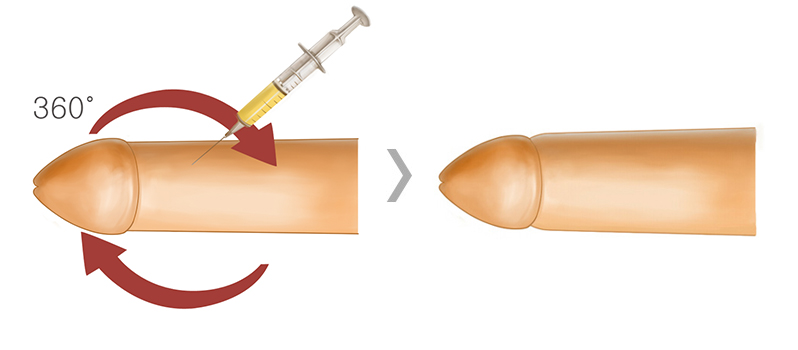

필 러

유로진은 액상형태인 필러 특성상 시술시 형태가

매우 중요하므로

상·중·하 피하층에 골고루

동시 주입하여 자연스러움과 확대효과를 높입니다

-

특 - 징

- 피부절개가 없는 비수술 확대

- 10여분 정도의 짧은 시술 진행

- 흉터 및 회복기간에 대한 부담이 거의 없음